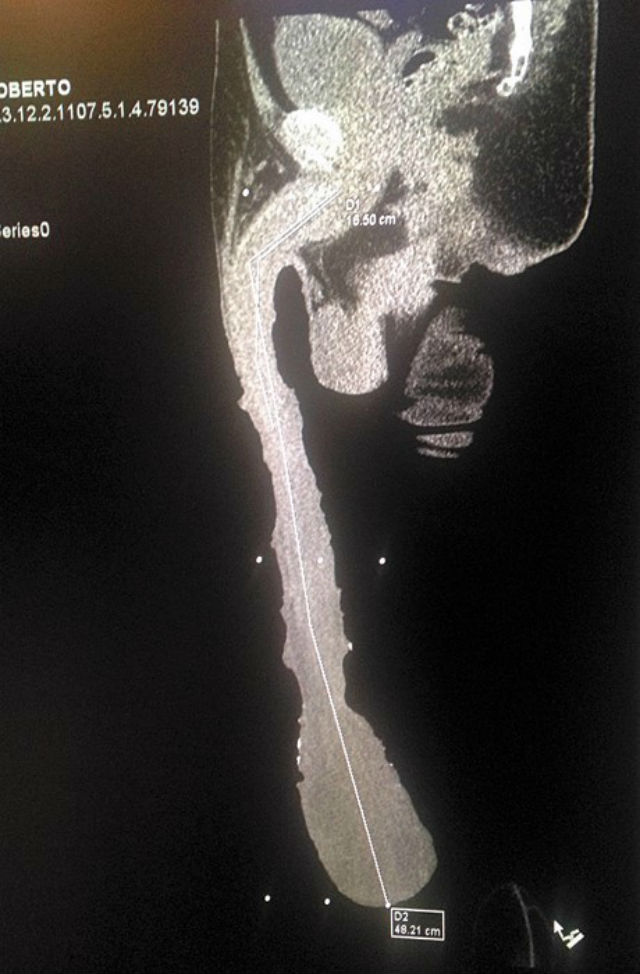

Bărbatul cu cel mai mare penis din istorie trăieşte o adevărată dramă. Mexicanul Roberto Esquivel Cabrera are 52 de ani, iar penisul lui uriaş este lung de 48,2 centimetri şi are circumferinţa de 25 de centimetri.

Cabrera nu se ştie însă deocamdată din ce cauză i-a crescut penisul în aşa hal. I s-au făcut radiografii, în urma cărora a rezultat clar că bărbatul nu are vreo proteză şi nu a folosit alte trucuri pentru a-şi mări bărbăţia. Însă medicii au observat că organul în sine ar fi mai mic, fiind acoperit în mare parte de mai multe straturi de piele, care măsoară 32 de centimetri.